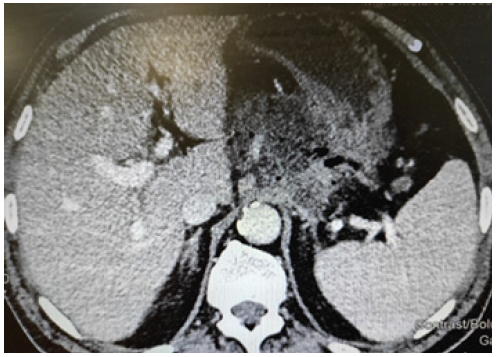

On the CT the necrosis of pancreas can be visualized at least 72 h after the beginning of this complication. This is the optimum time for initial CT scan (Figure 1) [3].

We should distinguish between different types of peripancreatic collections needed different treatments.

1) If the collection is homogenous on the CT, confined by normal tissues in the first week of onset of AP, we define this collection as Acute Peripancreatic Fluid Collection (APFC), which is usually sterile and resolve without intervention.

2) If the collection is heterogeneous, we associate this image with necrosis of pancreas. When the collection is less than 4 weeks old, we define it as an Acute Necrotic Collection (ANC), if present for greater than 4 weeks: Walled-Off Necrosis (WOPN). The necrosis needs an intervention [1].